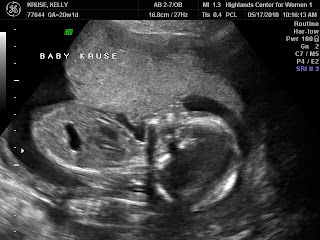

Oh boy, it's another girl.

Followin are today's ultrasound pics plus a picture of how I look today. The words out of the ultrasound tech's mouth were, "she looks fabulous."  Regarding all that they look at to make sure this is a healthy and well developed baby. We couldn't be any happier!!  It's another perfect little girl.  And I'm so happy Stella will have a sister to grow up and to grow old with.  Name is chosen, but we will be keeping it a secret.  You'll just have to wait.  P.S.  This makes for the 8th granddaughter of 8 grandchildren.  No grandsons.  What are the odds?